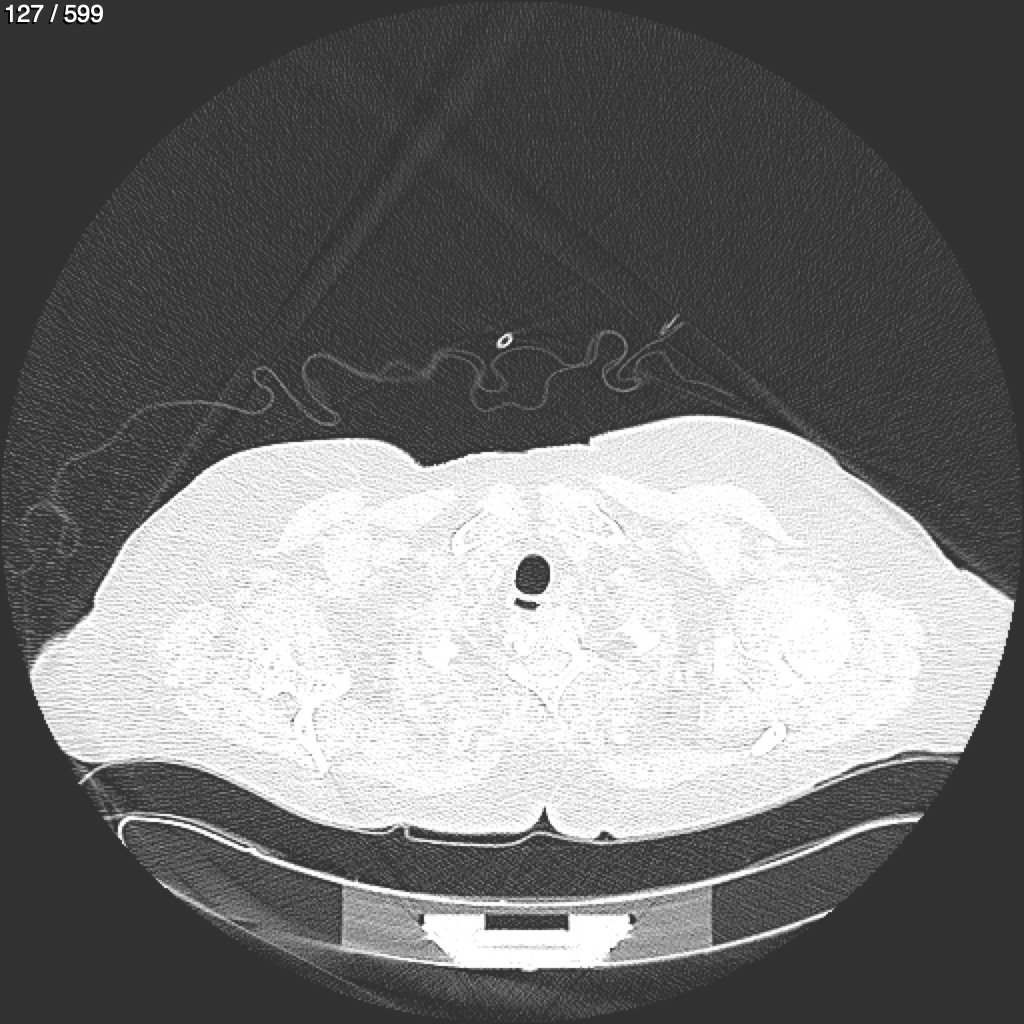

Home G​l​o​r​i​a​ ​G​l​a​d​y​s​ ​B​e​a​s​l​e​y​ ​-​ ​T​ó​r​a​x​ ​T​o​r​a​x​_​S​i​m​p​l​e​ ​(​A​d​u​l​t​o​)